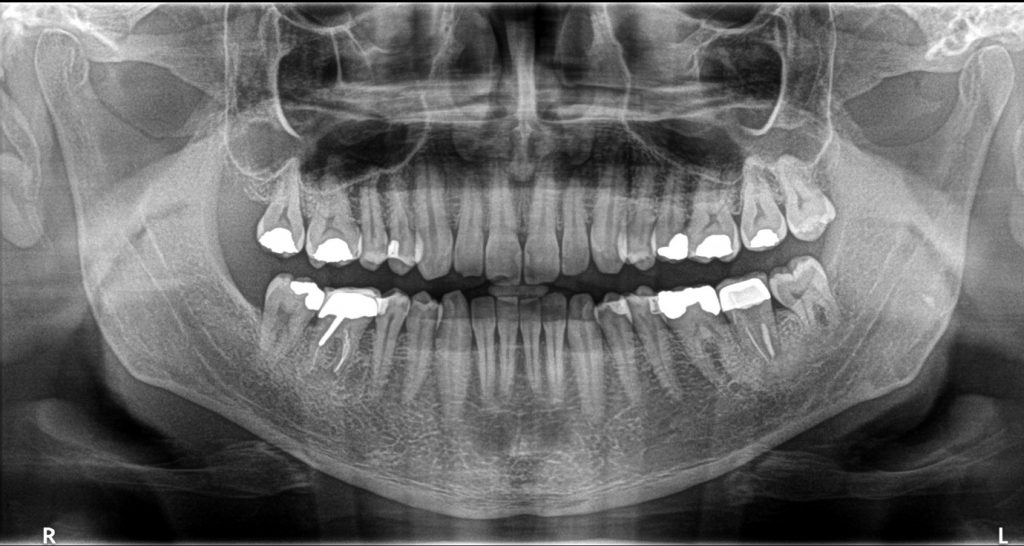

رادیوگرافی اولیه که نشان دهنده رویش کامل دندانهای عقل در سمت راست تصویر و عدم نیاز ان ها به کشیدن میباشد. در سمت چپ دندانهای عقل به علت کمبود فضا و عدم رویش کامل قبلا کشیده شده بودند.